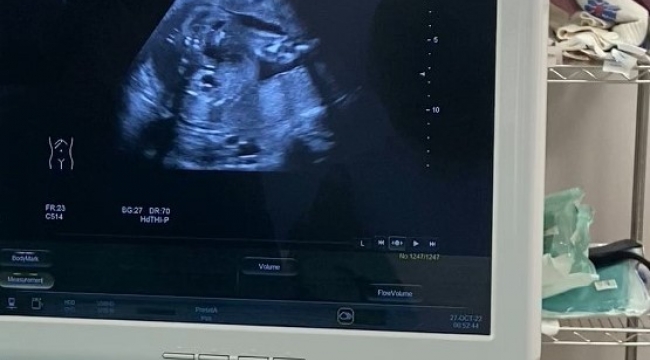

Elazığ'da anne karnında idrar çıkış yolu darlığı tespit edilen bebeğe stent takılarak idrarını yapması sağlandı.

Fethi Sekin Şehir Hastanesi Perinatoloji Polikliniğine müracaat eden gebenin bebeğinde idrar yolu darlığı tespit edildi. Perinatoloji uzmanı tarafından yapılan detaylı muayene ve tetkiklerden sonra anne, bebek sağlığı için bebeğe stent takılması gerektiği belirlendi. Ultrason eşliğinde Vesicoamniyotik Stent takılan bebeğin idrarını yapması sağlandı.

Uygulanan işlemin oldukça hassas olduğunu ifade eden Perinatoloji Uzmanı Dr. Birsen Konukçu Palta, "Vesicoamniyotik Stent uygulması ile bebeğin idrar kesesine takılan bir kanül ile idrarını yapması sağlanır. Bu işlemin amacı bebeğin anne karnında içinde bulunduğu suyun devamlılığını sağlamaktır. Bize başvuran gebemizin bebeğinde idrar yolu darlığı tespit ettik. Öncelikle amniyosentez işlemi ile bebeğin genetiğinin normal olduğunu ve yaptığımız tetkiklerde böbreklerinin hala çalışır vaziyette olduğu belirledik. Şant yapılmasına karar verdiğimiz hastamıza sınırlı bir uyuşturma altında işlemimizi uyguladık. Ultrason eşliğinde yapılan işlem sonucunda bebeğimizin idrarını yapmasını sağladık" dedi.